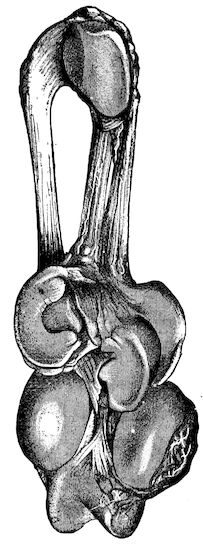

| Castration of the cow | 761 | |||

| Castration of the sow | 765 | |||